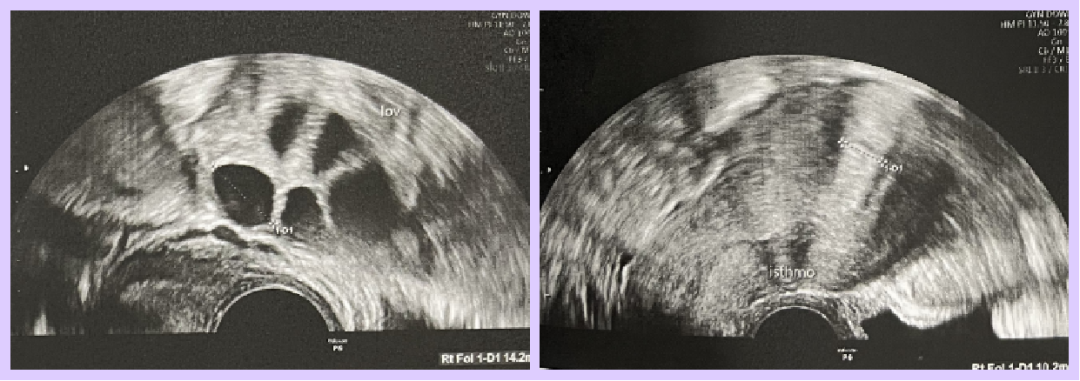

- Day 15 of Menstrual Cycle (Thailand)

- Hormone Levels:

- Estradiol: 241.1 pg/mL

- Progesterone: 0.15 ng/mL

- Ultrasound Findings: Endometrial thickness 12.5–13.9 mm

- Treatment Plan: Estradiol valerate (Progynova), aspirin, prednisone, dydrogesterone, vaginal progesterone suppositories, Ventolin, estradiol gel

Additionally, the patient’s history of cesarean sections may have resulted in a uterine scar diverticulum (isthmocele), with fluid accumulation observed at this site. This fluid could elevate inflammation risks and interfere with embryo implantation in the endometrium. The patient also has endometrial polyps, which may hinder embryo implantation by disrupting the endometrial environment, further reducing IVF success rates.

Preparation: Hysteroscopy was performed to remove endometrial polyps, followed by a one-month rest period before preparing the endometrial cycle.